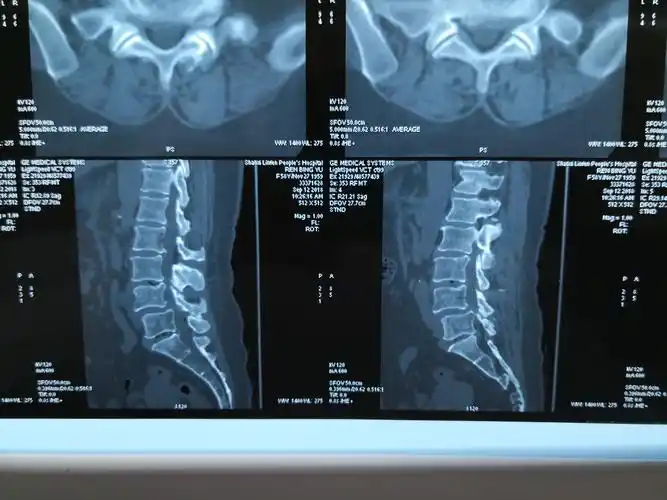

腰椎ct